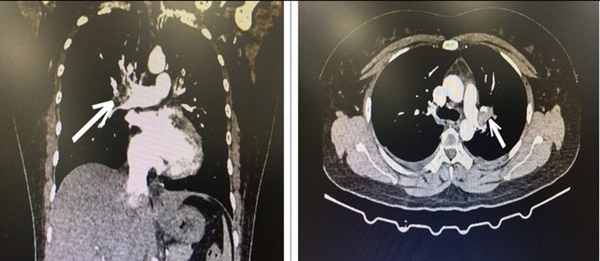

Khi vào bệnh viện, bệnh nhân đã được chỉ định xét nghiệm cấp cứu, siêu âm tim có hình ảnh giãn buồng tim phải, hở nặng van 3 lá, tăng áp lực động mạch phổi. Các bác sĩ cấp cứu hướng chẩn đoán tới bệnh thuyên tắc động mạch phổi cấp và quyết định cho chụp CT ngực có tiêm thuốc cản quang, kết quả là hình ảnh huyết khối động mạch phổi 2 bên.

Hình ảnh CT lồng ngực bệnh nhân bị tắc động mạch phổi cấp tính. Ảnh: BVCC